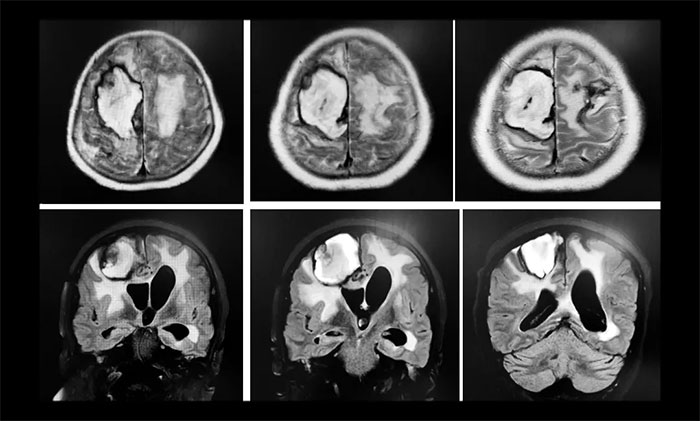

两次癫痫发作后,王阿姨陷入昏迷,再也没有醒来,并且生命体征不稳定,上了呼吸机,体温偏高,一直降不下来,医院给予相关对症治疗,但未有好转,如此一直持续了20天左右。直到7月11号,在做了CT后,医生发现脑占位,考虑肿瘤。“20天前,CT检查什么都没有,现在怎么会有肿瘤?”孙大叔提出质疑。之后行MRI示右侧额顶叶、基底节区及左侧额叶、左侧侧脑室出现大面积积血、脑水肿;MRV示右侧横窦、乙状窦、颈内静脉未见明确显示。医院影像科主任阅片后考虑静脉窦血栓。而此时距王阿姨发病已经过去了20天,错过了介入取栓时间窗,只能选择保守治疗。在住院治疗 42天后,王阿姨意识仍未恢复,还出现肺部感染,之后她辗转了多家医院。

▲ 入院时,行头颅MRI示:静脉窦血栓导致右侧额顶叶、基底节区及左侧额叶大面积出现脑积血、脑水肿

入院时,查体:患者中度昏迷状,右侧偏瘫,肌力II+级,右下肢肌张力高,右侧巴彬斯基征(阳性)。诊断:颅内静脉窦血栓形成、静脉性梗死并梗死后出血、肺部感染、继发性癫痫、低蛋白血症。